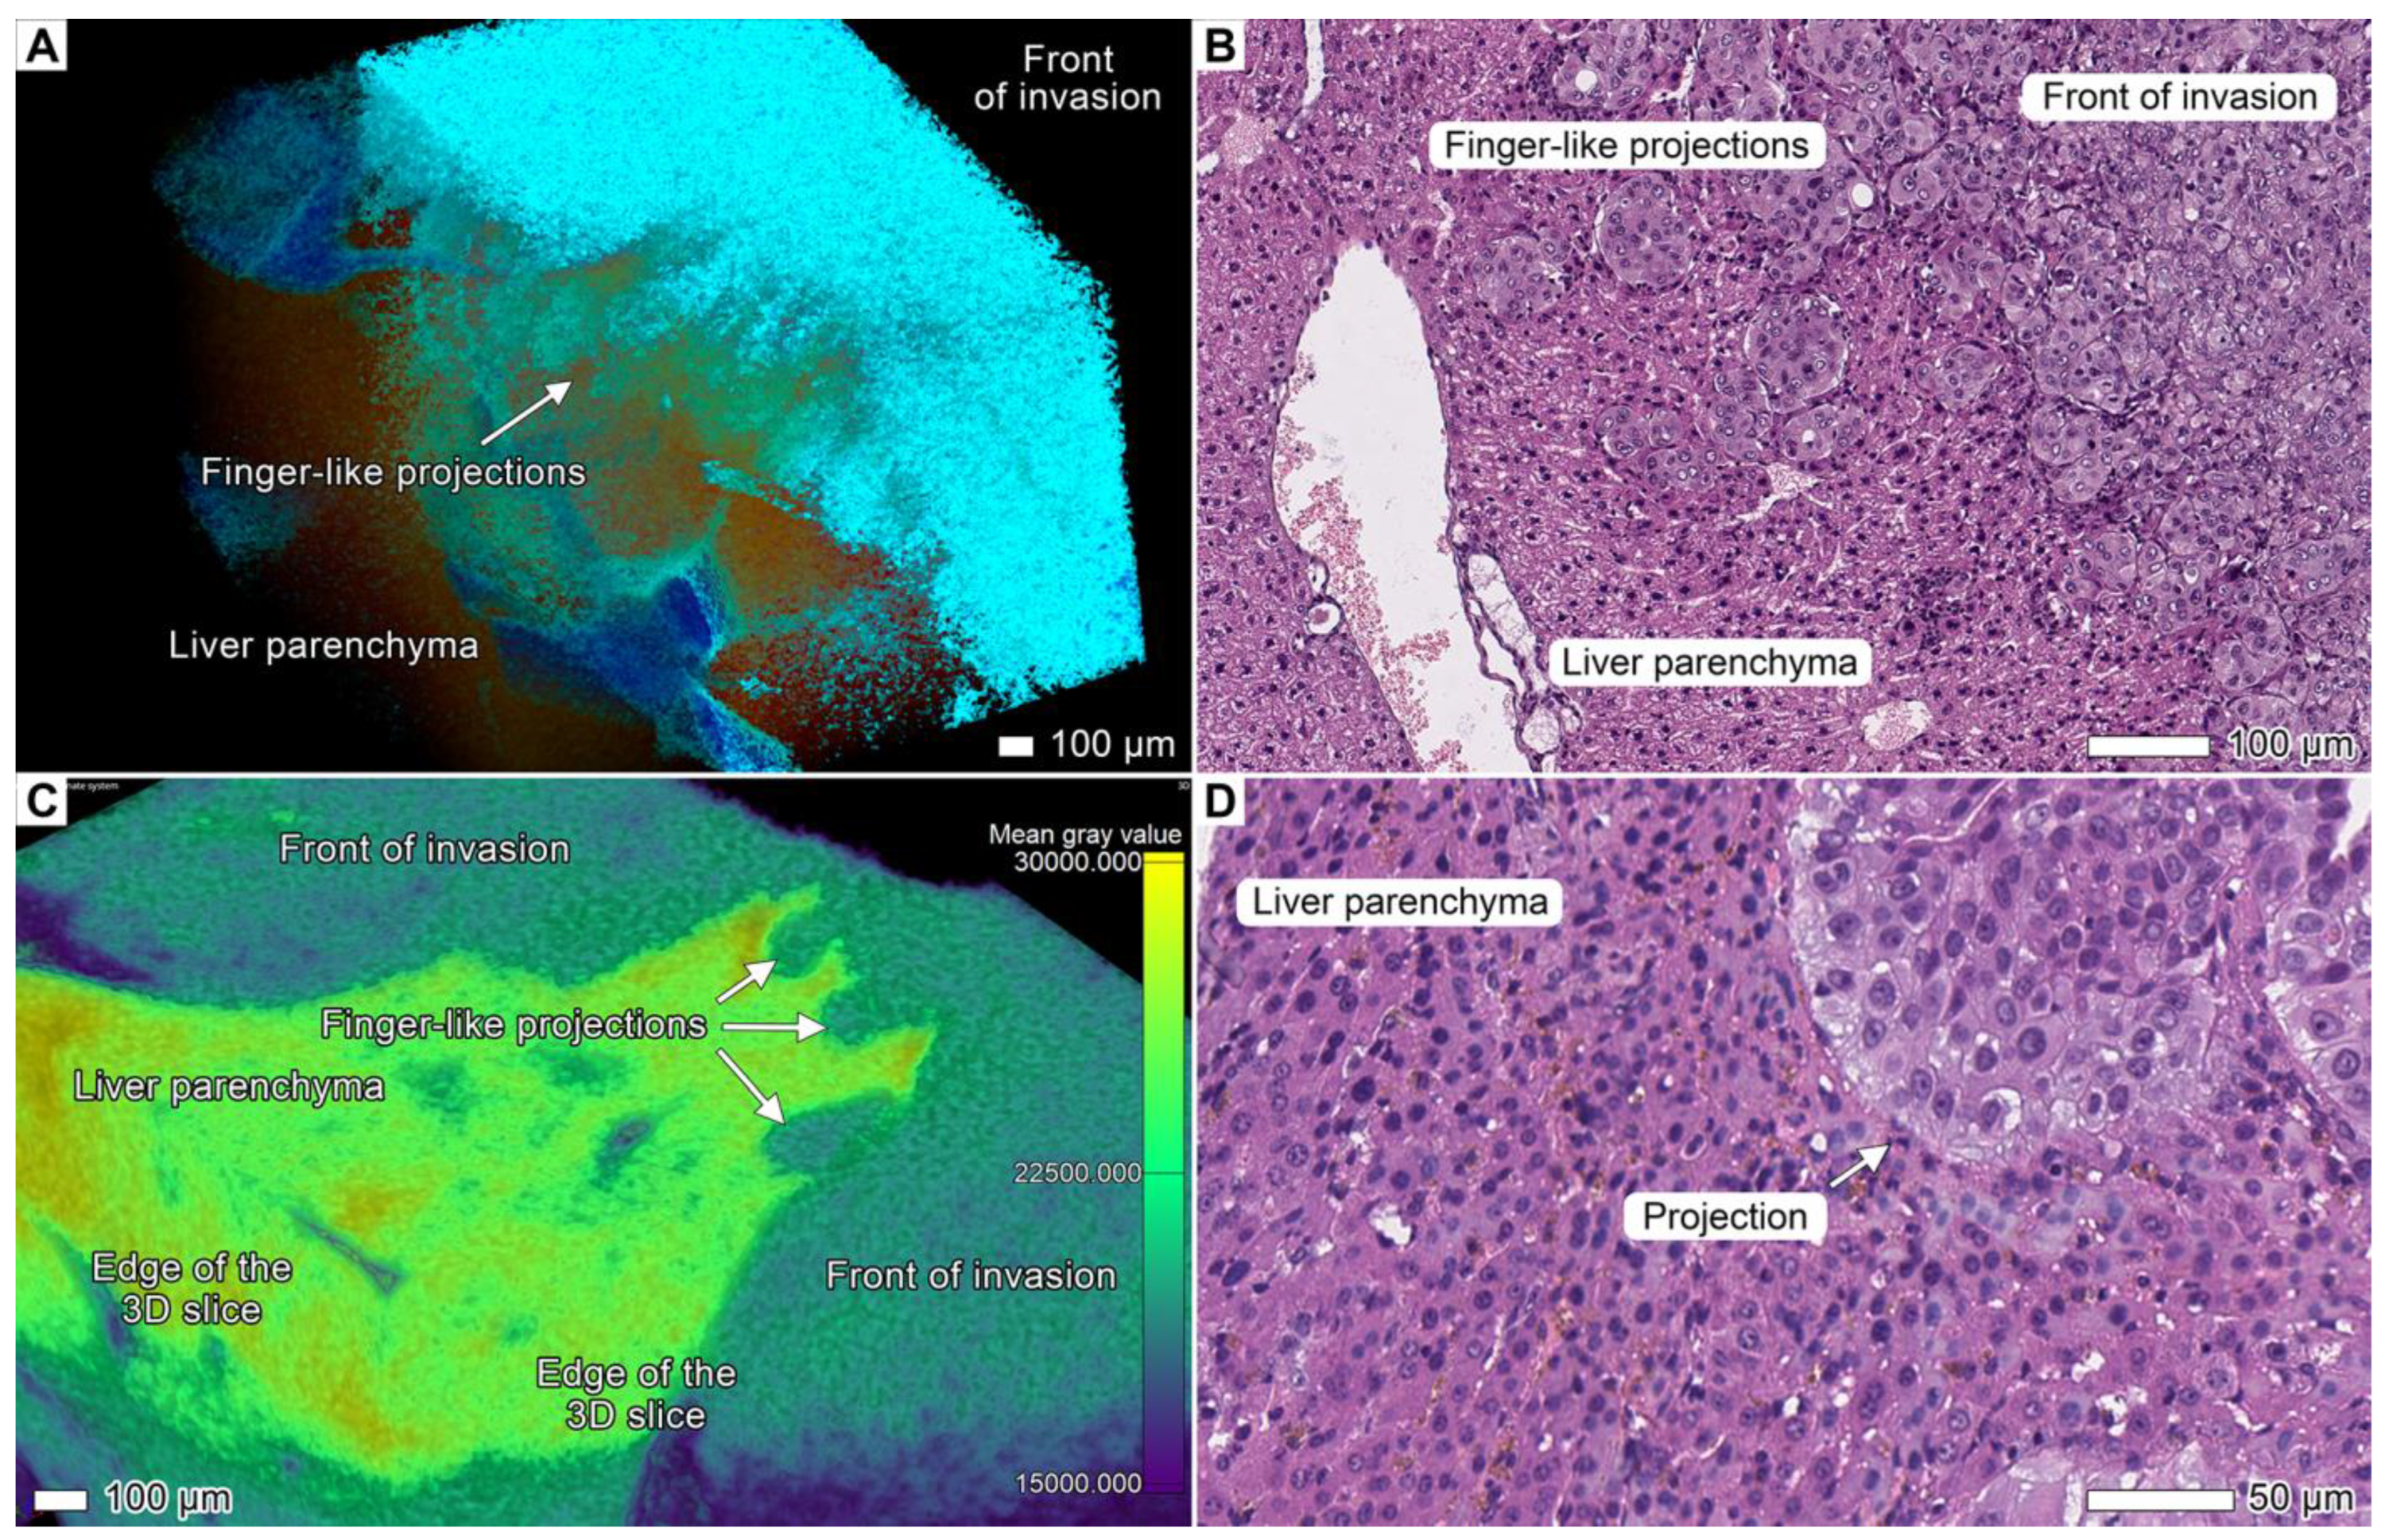

3.5. Tumor Invasion into the Liver

4.7. The Finger-like Projection Type of Invasion in the Connective Tissue